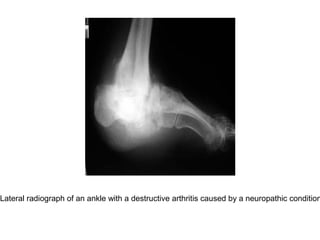

Lateral radiograph of an ankle with a destructive arthritis caused by a neuropathic condition

Lateral radiograph ofan ankle with a destructive arthritis caused by a neuropathic condition